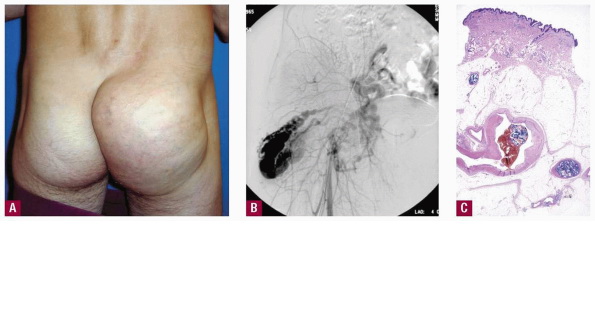

Arsenical keratoses = التقران الزرنيخي ARSENICAL KERATOSES Arsenical keratoses (ArKs) are precancerous lesions found in association with chronic arsenicism. These lesions have the potential to develop into invasive SCC. Arsenic is a ubiquitous element that has no color, taste, or odor. It has the potential to cause characteristic acute and chronic syndromes in persons exposed […]